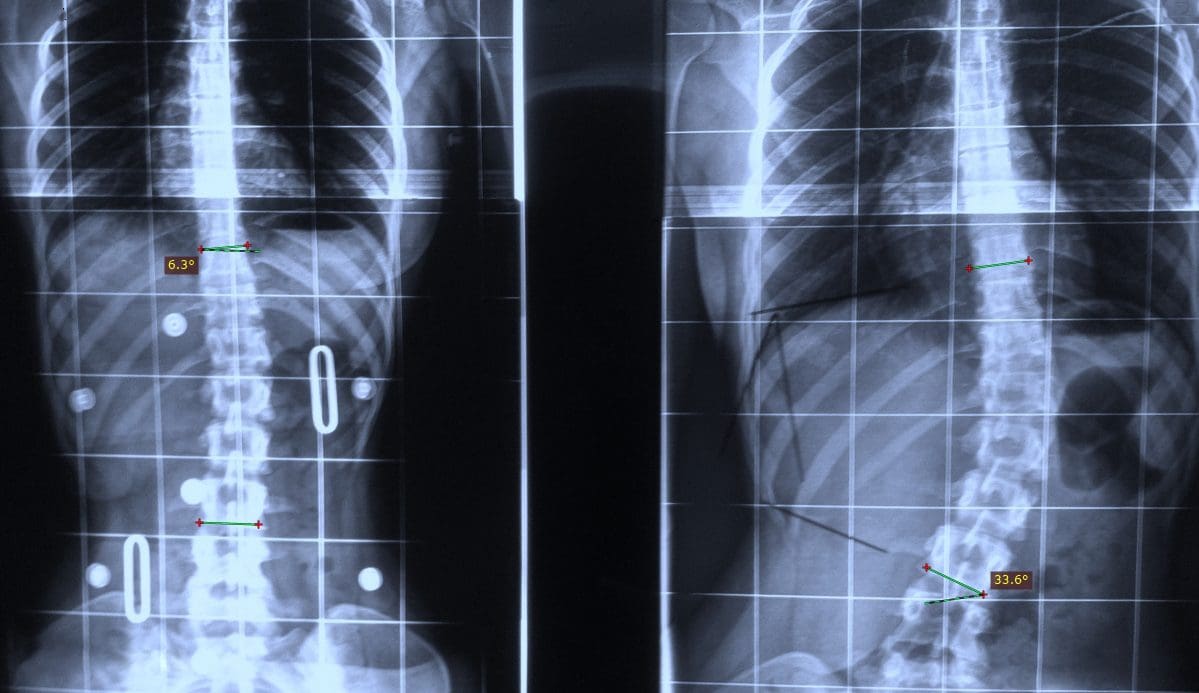

Studji dwar l-Immaġini

L-immaġini f'mard deġenerattiv tad-diska tintuża prinċipalment biex tiddeskrivi relazzjonijiet anatomiċi u karatteristiċi morfoloġiċi tad-diski affettwati, li għandha valur terapewtiku kbir fit-teħid ta 'deċiżjonijiet futuri għal għażliet ta' trattament. Kwalunkwe metodu ta 'immaġini, bħal radjografija sempliċi, CT, jew MRI, jista' jipprovdi informazzjoni utli. Madankollu, kawża sottostanti tista 'tinstab biss fi 15% tal-pazjenti billi l-ebda bidliet radjoloġiċi ċari ma huma viżibbli f'mard deġenerattiv tad-diska fin-nuqqas ta' ħernja tad-diska u defiċit newroloġiku. Barra minn hekk, m'hemm l-ebda korrelazzjoni bejn il-bidliet anatomiċi li dehru fuq l-immaġini u s-severità tas-sintomi, għalkemm hemm korrelazzjonijiet bejn in-numru ta 'osteofiti u s-severità ta' uġigħ fid-dahar. Bidliet deġenerattivi fir-radjografija jistgħu jidhru wkoll f'nies bla sintomi li jwasslu għal diffikultà biex jikkonformaw ir-rilevanza klinika u meta tibda l-kura. ("Marda tad-Diska Deġenerattiva" Fiżjopedja)

Ir-Radjografija

Din ir-radjografija ċervikali sempliċi rħisa u disponibbli b'mod wiesa 'tista' tagħti informazzjoni importanti dwar id-deformitajiet, l-allinjament, u bidliet deġenerattivi taż-żaqq. Sabiex tiġi ddeterminata l-preżenza ta 'instabilità ta' l-ispina u bilanċ sagittali, għandhom isiru studji ta 'flessjoni dinamika jew estensjoni.

Immaġini b'Reżonanza Manjetika (MRI)

L-MRI huwa l-iktar metodu użat komunement għad-dijanjosi ta 'bidliet deġenerattivi fid-diska intervertebrali b'mod preċiż, affidabbli, u l-iktar komprensiv. Jintuża fl-evalwazzjoni inizjali ta 'pazjenti b'uġigħ fl-għonq wara radjografija sempliċi. Jista 'jipprovdi immaġini mhux invażivi f'diversi pjanuri u jagħti immaġini ta' kwalità eċċellenti tad-diska. L-MRI tista 'turi l-idratazzjoni tad-diska u l-morfoloġija bbażata fuq id-densità tal-proton, l-ambjent kimiku, u l-kontenut ta' ilma. L-istampa klinika u l-istorja tal-pazjent għandhom jiġu kkunsidrati meta jiġu interpretati r-rapporti tal-MRI peress li ntwera li sa 25% tar-radjoloġisti jibdlu r-rapport tagħhom meta d-dejta klinika tkun disponibbli. Fonar ipproduċa l-ewwel skaner MRI miftuħ bil-kapaċità tal-pazjent li jiġi skannjat f'pożizzjonijiet differenti bħal wieqaf, bilqiegħda u liwi. Minħabba dawn il-karatteristiċi uniċi, dan l-iskaner MRI miftuħ jista 'jintuża għall-iskannjar ta' pazjenti f'qagħdiet li jġorru l-piż u qagħdiet bil-wieqfa biex jindividwaw bidliet patoloġiċi sottostanti li ġeneralment jiġu injorati fl-iskan MRI konvenzjonali bħal mard deġenerattiv tal-ġenbejn bil-ħernja. Din il-magna hija tajba wkoll għal pazjenti klawstrofobiċi, peress li huma jaraw skrin kbir tat-televiżjoni waqt il-proċess tal-iskannjar. ("Marda tad-Diska Deġenerattiva: Sfond, Anatomija, Patofiżjoloġija.")

Nucleus pulposus u annulus fibrosus tad-diska jistgħu ġeneralment jiġu identifikati fuq l-MRI, u dan iwassal għall-iskoperta ta 'herniation tad-diska bħala kontenuta u mhux kontenuta. Peress li l-MRI tista 'turi wkoll tiċrit annulari u l-ligament lonġitudinali posterjuri, tista' tintuża biex tikklassifika l-herniation. Dan jista 'jkun minfuq annulari sempliċi biex tittrasferixxi l-hernjazzjonijiet tad-diska tal-frammenti. Din l-informazzjoni tista 'tiddeskrivi diski patoloġiċi bħal diski estrużi, diski maħruġa u diski migrati.

Hemm diversi sistemi ta 'klassifikazzjoni bbażati fuq l-intensità tas-sinjal MRI, l-għoli tad-diska, id-distinzjoni bejn in-nukleu u l-annulus, u l-istruttura tad-diska. Il-metodu, minn Pfirrmann et al, ġie applikat b'mod wiesa 'u aċċettat klinikament. Skont is-sistema modifikata, hemm 8 gradi għall-mard deġenerattiv tad-diska lumbari. Il-Grad 1 jirrappreżenta diska intervertebrali normali u l-grad 8 jikkorrispondi mal-istadju tat-tmiem tad-deġenerazzjoni, li juri l-progressjoni tal-marda tad-diska. Hemm immaġini korrispondenti biex jgħinu d-dijanjosi. Peress li jipprovdu differenzjazzjoni tajba tat-tessut u deskrizzjoni dettaljata ta 'l-istruttura tad-diska, l-immaġini mgħobbija T2 sagittali jintużaw għall-iskop tal-klassifikazzjoni. (Pfirrmann, Christian WA, et al.)